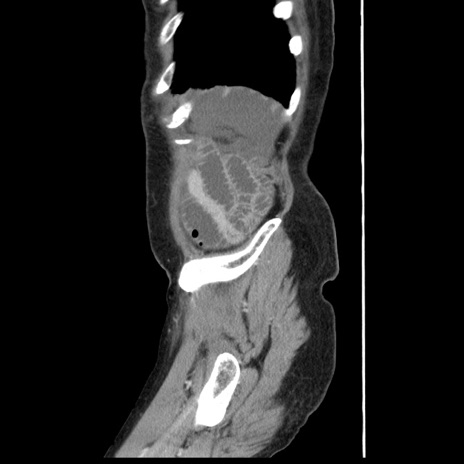

症例1(矢状断像)

【症例】80歳代女性

【主訴】腹痛

【現病歴】8時間前から腹痛あり来院。

【既往歴】糖尿病、脂質異常症、子宮体癌にて子宮全摘術

【身体所見】意識清明・会話良好だが腹痛で苦悶様、全腹部にわたって反跳痛と圧痛あり

【データ】WBC 13600、CRP 0.14、LDH 224、CK 90